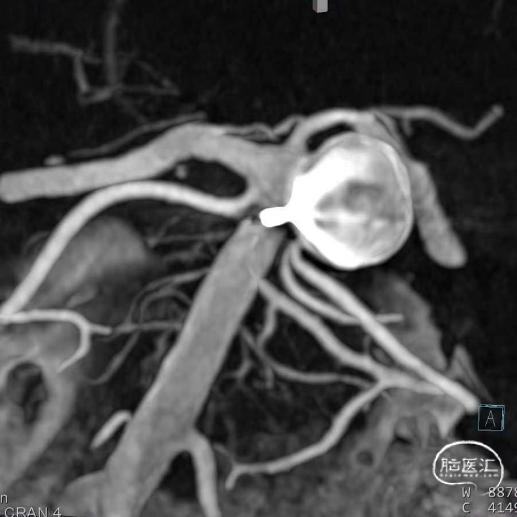

动脉瘤一:基底动脉末端动脉瘤

动脉瘤一:基底动脉末端动脉瘤,由左侧大脑后动脉与左侧小脑上动脉瘤夹角处动脉瘤形成且为不规则状;瘤体上有子囊形成,左侧小脑上动脉从近心端瘤颈处动脉瘤瘤体上发出,动脉瘤与载瘤动脉近直角。

经测量可得动脉瘤宽度平均值为8.88mm,动脉瘤最小高度为7.71mm,瘤颈约为4.03mm。参考尺寸选择表,选择WEB™ SL 10*5,VIA™ 33微导管。